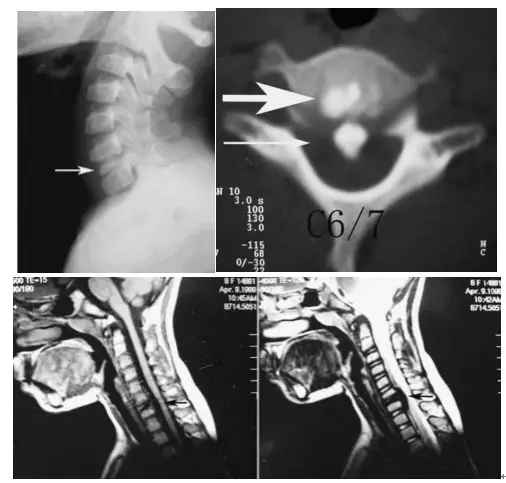

圖:患者8歲,女孩,因嚴重頸部疼痛、活動受限伴左上肢無力、麻木不適2天就診。既往有鎖骨骨折、額部軟組織挫傷病史。查體:頸椎活動受限,左上肢肌力正常,但感覺減退。白細胞、血沉、CRP升高。頸椎側位片和CT平掃提示C6-7椎間盤鈣化(粗箭頭)和後縱韌帶骨化(細箭頭),頸椎MRI提示C6-7水平脊髓明顯受壓。給予頸椎制動、枕頜帶2.5kg頸椎牽引2周。隨後,頸託固定1個月。2年後隨訪複查頸椎CT如下圖,同時上述症狀完全緩解。

圖:2年後複查CT示C6-7鈣化的椎間盤和後縱韌帶骨化都消失了

【病例2】

圖:8歲女孩,因頸腰痛伴左上肢放射痛2月餘就診,頸椎側位片、CT和MRI表現與上述病例類似。